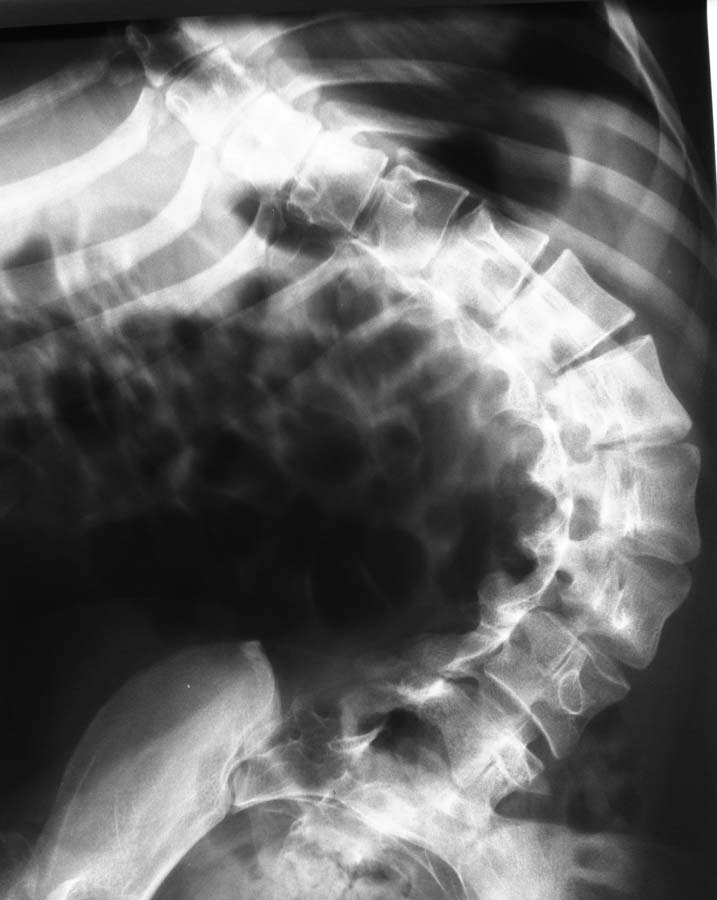

ДЦП, Сколиоз и вывих бедра.

Пациентка 1992 г.р. Болеет ДЦП с рождения. до 2005 г. наблюдалась у неврологов , ходила с поддержкой. В 2005 г. перелом средней трети бедра. Лечилась консервативно в больнице Краснодара.

После лечения постепенно стало наростать укорочение конечности и искривление позвоночника.На представленных Р-гр состояние на сегодняшний день.больная занимает вынужденное полулежачее состояние.Вопрос - где нибудь на просторах РФ могут помочь?????